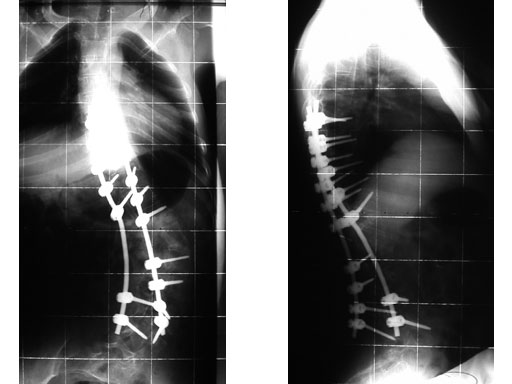

A 23-year-old man with neurogenic kyphoscoliosis, Cobb angle: 120. Fusion of T7S1 with universal reduction screws. Duration of surgery: 4.5 hours.